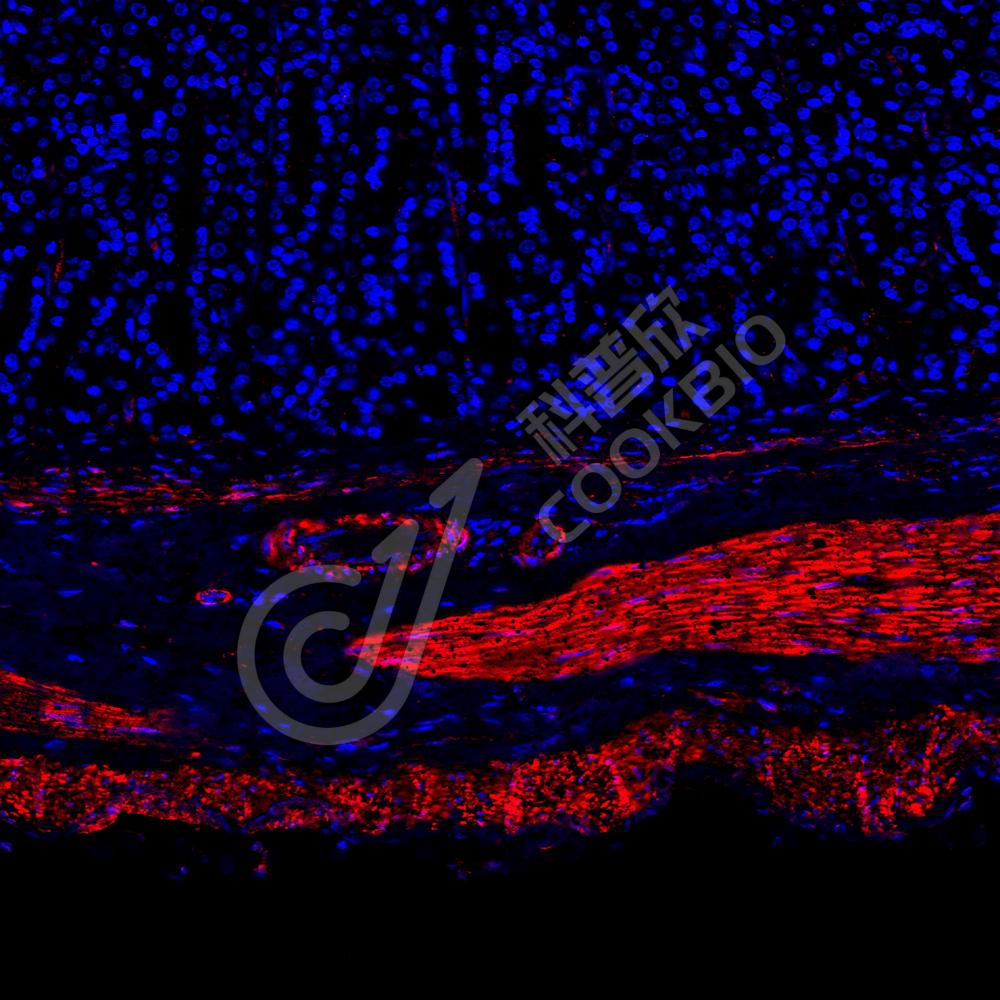

IF检测Desmin蛋白(货号 K236225)(红色).

样品: 人胃, 4%多聚甲醛 (货号KSG1101) 固定12-24小时.

抗原修复: 柠檬酸抗原修复液(干粉, pH 6.0) (KSG1201), 高压锅均匀喷气计时2分钟.

封闭: 3% BSA(货号KSGC305010)的PBS溶液, 室温孵育30分钟.

—抗: 1: 1300稀释, 4℃ 孵育过夜.

二抗: Cy3标记山羊抗小鼠IgG (H+L) (货号KB63903), 1: 300稀释, 室温孵育1小时.